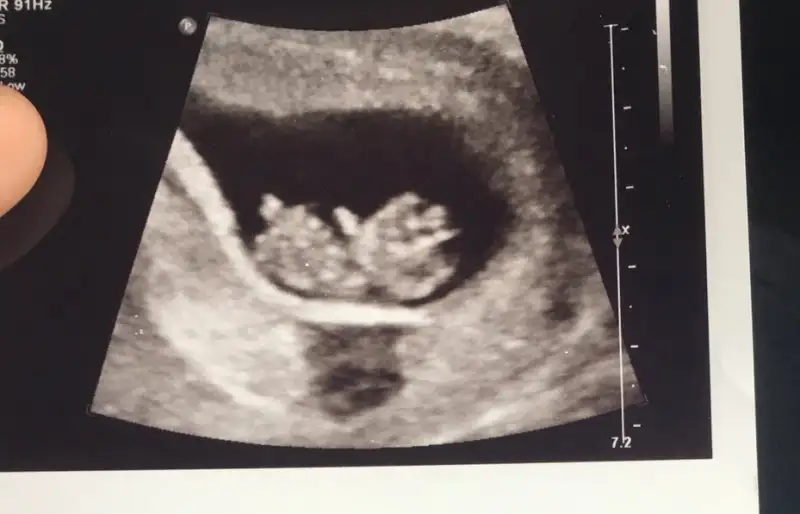

Ya bende tam 9+3 de gidicem heyecandan kalbim pır pır şimdi benim minnoşumdamı böyle görünecek allahın izniyle rabbim yavrularımızı bize bağışlasınMelegim bu kızlar bugün 9+6 olduk resimde 9+3 günlük. Altındaki yuvarlak kanama alanımdı çok şükür kanama da kahverengi akıntıda durdu.

Canım maşallah çok güzel görünüyor. 9. Haftada baya büyüyorlar demek ki allah sağlıkla tamamına erdirsin inşallahMelegim bu kızlar bugün 9+6 olduk resimde 9+3 günlük. Altındaki yuvarlak kanama alanımdı çok şükür kanama da kahverengi akıntıda durdu.

oyy kıyamam allah bağışlasın. ben de 11 haftalıkken gideceğim kontrole kim bilir ne kadar büyümüş olur, bi an önce zaman geçsin de göreyim yavrumu istiyorum :)Melegim bu kızlar bugün 9+6 olduk resimde 9+3 günlük. Altındaki yuvarlak kanama alanımdı çok şükür kanama da kahverengi akıntıda durdu.

Masallah insallah saglikla kucagina alirsinMelegim bu kızlar bugün 9+6 olduk resimde 9+3 günlük. Altındaki yuvarlak kanama alanımdı çok şükür kanama da kahverengi akıntıda durdu.